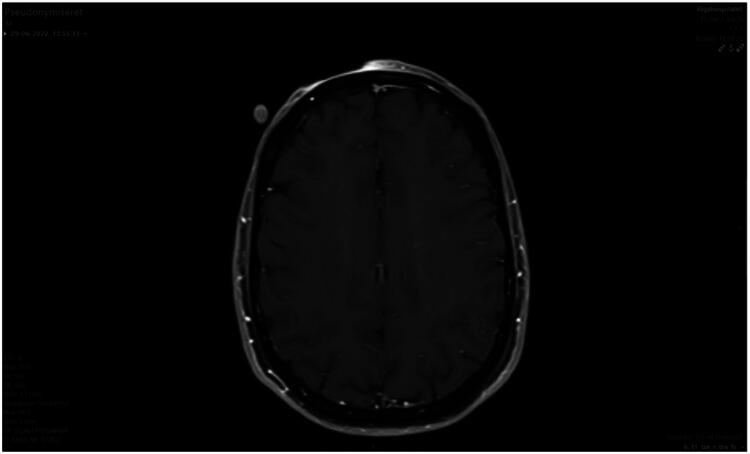

隆突性皮肤纤维肉瘤(DFSP)是一种罕见的局部侵袭性皮肤肿瘤,主要影响年轻人到中年人,其特征是生长缓慢,硬化斑块或结节。由于其罕见,生长模式和临床表现多变,DFSP的诊断和治疗具有挑战性。男性,40岁,额上硬肿块8毫米,一年。它最初被怀疑是良性脂肪瘤或动脉粥样硬化,并由私人整形外科医生切除。然而,组织病理学检查显示结节性皮肤纤维肉瘤(DFSP)未被彻底切除,提示转介到我科切除。在这里,他表现为一个10毫米的疤痕,没有可见或可触及的残余肿瘤。计划切除20 mm,并进行分厚皮移植重建。组织病理学显示肿瘤在几个边缘有活动,神经周围和骨膜浸润。MRI不确定,因此加上PET-CT,显示可能残留肿瘤。再次切除包括定位活检。为了获得清晰的手术边缘,进行了三次广泛的再切除,肿瘤大小约为8 × 10厘米,最终缺损尺寸为10 × 12厘米。缺损用真皮模板(Integra®)和STSG重建。我们的病例强调了DFSP明显的亚临床延伸倾向,包括潜在的神经周围和骨膜侵犯。尽管在美学上具有挑战性的位置,取得了令人满意的美容效果,并在两年的随访期间没有复发。

Dermatofibrosarcoma protuberans (DFSP) is a rare, locally aggressive cutaneous tumor predominantly affecting young to middle-aged adults, characterized by a slow-growing, indurated plaque or nodule. The diagnosis and treatment of DFSP can be challenging due to its rarity, growth pattern and variable clinical presentation. A 40-year-old male presented with a firm lump of 8 mm on his forehead for one year. It was initially suspected to be a benign lipoma or atheroma and removed accordingly by a private plastic surgeon. However, histopathological examination revealed dermatofibrosarcoma protuberans (DFSP) that was not radically removed, prompting referral for removal at our department. Here, he presented with a scar of 10 mm with no visible or palpable residual tumor. A planned excision of 20 mm and reconstruction with split thickness skin graft (STSG) was performed. Histopathology showed tumor activity at several margins, with perineural and periosteal invasion. MRI was inconclusive, and therefore PET-CT was added, which showed possible residual tumor. Re-excision including mapping biopsies was performed. Wide re-excision was performed three times to achieve clear surgical margins, yielding a tumor size of approximately 8x10 cm and a final defect measuring 10x12 cm. The defect was reconstructed with a dermal template (Integra®) and STSG. Our case underscores the propensity of DFSP for significant subclinical extension, including potential perineural and periosteal invasion. Despite the aesthetically challenging location, a satisfactory cosmetic result was achieved, and there was no recurrence during the two-year follow-up.